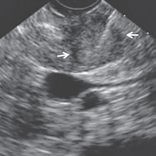

The EUS showed a hypoechoic and homogeneous nodule within precise limits, located in the uncinate process. The lesion measured 2.2x1.8cm in length. The Doppler signal was negative. The lesion was distant from the main pancreatic duct and the common bile duct. The FNA was performed with the Expect™ Needle (22G) with a large amount of material that was sent to microhystology (Figure 1).